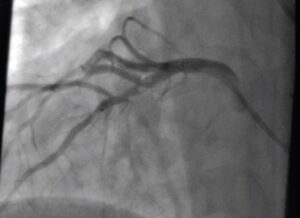

cardiac cath april 2024

By Jed Henson | on April 4, 2024 | 0 Comment